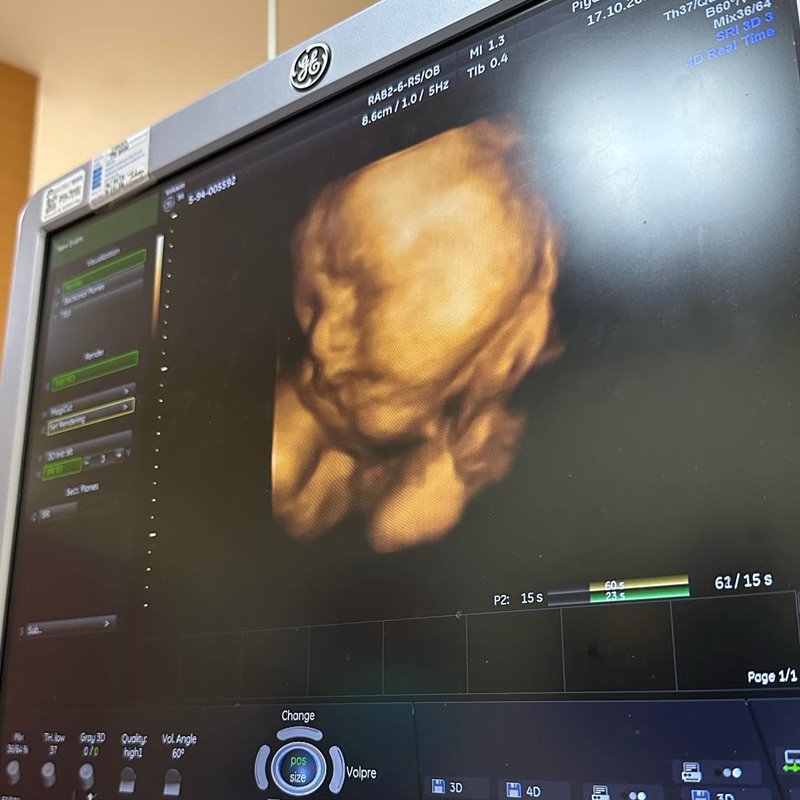

ก่อนที่ล่าสุด บุ๋ม ปนัดดา จะเผยภาพแรกของลูกชาย น้องอเล็กซ์ ถ่ายกับคุณพ่อคุณแม่แบบพร้อมหน้าหลังคลอด พร้อมข้อความเปิดตัวลูกชาย กับความรู้สึกแรกที่ได้ยินเสียงน้อง ระบุว่า...

"น้อง อนันท์ อนันทวรรณ

ชื่อเล่น อเล็กซ์ Alex

เกิด 22/11/22 เวลา 11:11น.

น้ำหนัก 2.966 ความยาว 50 ซม.